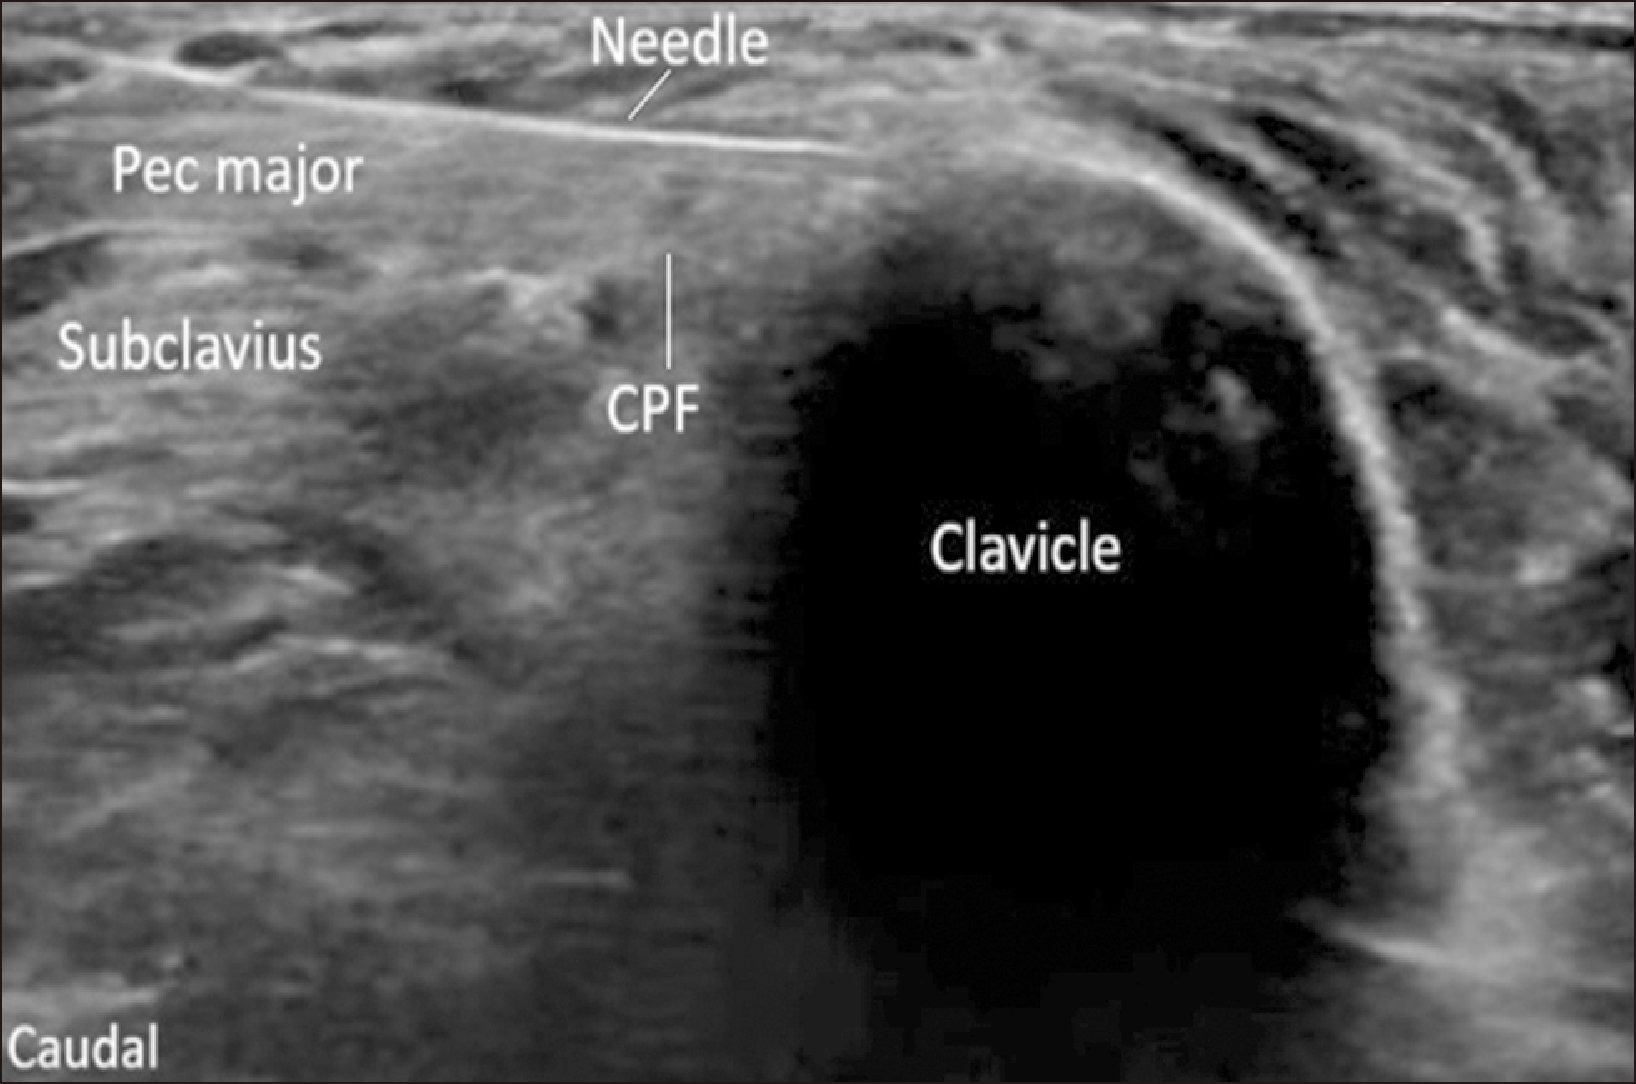

Patients were positioned supine semi-recumbent, with the head and back supported. The anesthetist stood adjacent to the patient's head, with the ultrasound machine on the opposite side. After crossing the deep cervical fascia, the operator scanned the SCN on the outer border of the sternomastoid muscle, which was 2–3 cm from the clavicle. The skin was prepared with 1 mL of lidocaine 1%, and a sterile 22-gauge blunt 50 mm needle was advanced close to the nerve using the in-plane technique [16]. The local anesthetic mixture of 2 mL was injected in 0.5 mL aliquots after ensuring no blood was aspirated to encircle the SCN (Fig. 1).

Fig. 1

Ultrasonographic image of the SCN block. The needle is advanced close to the nerve using the in-plane technique. SCN: supraclavicular nerve, SCM: sternocleidomastoid muscle, C5: fifth cervical nerve root, C6: sixth cervical nerve root, ASM: anterior scalene muscle, MSM: middle scalene muscle.